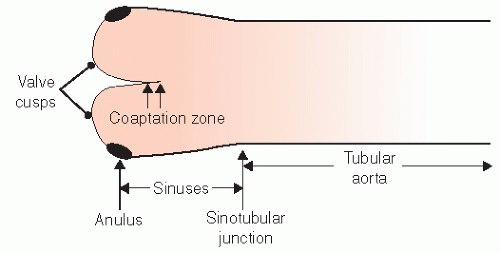

Нормальный диаметр корня аорты: медицинские нормы и отклонения